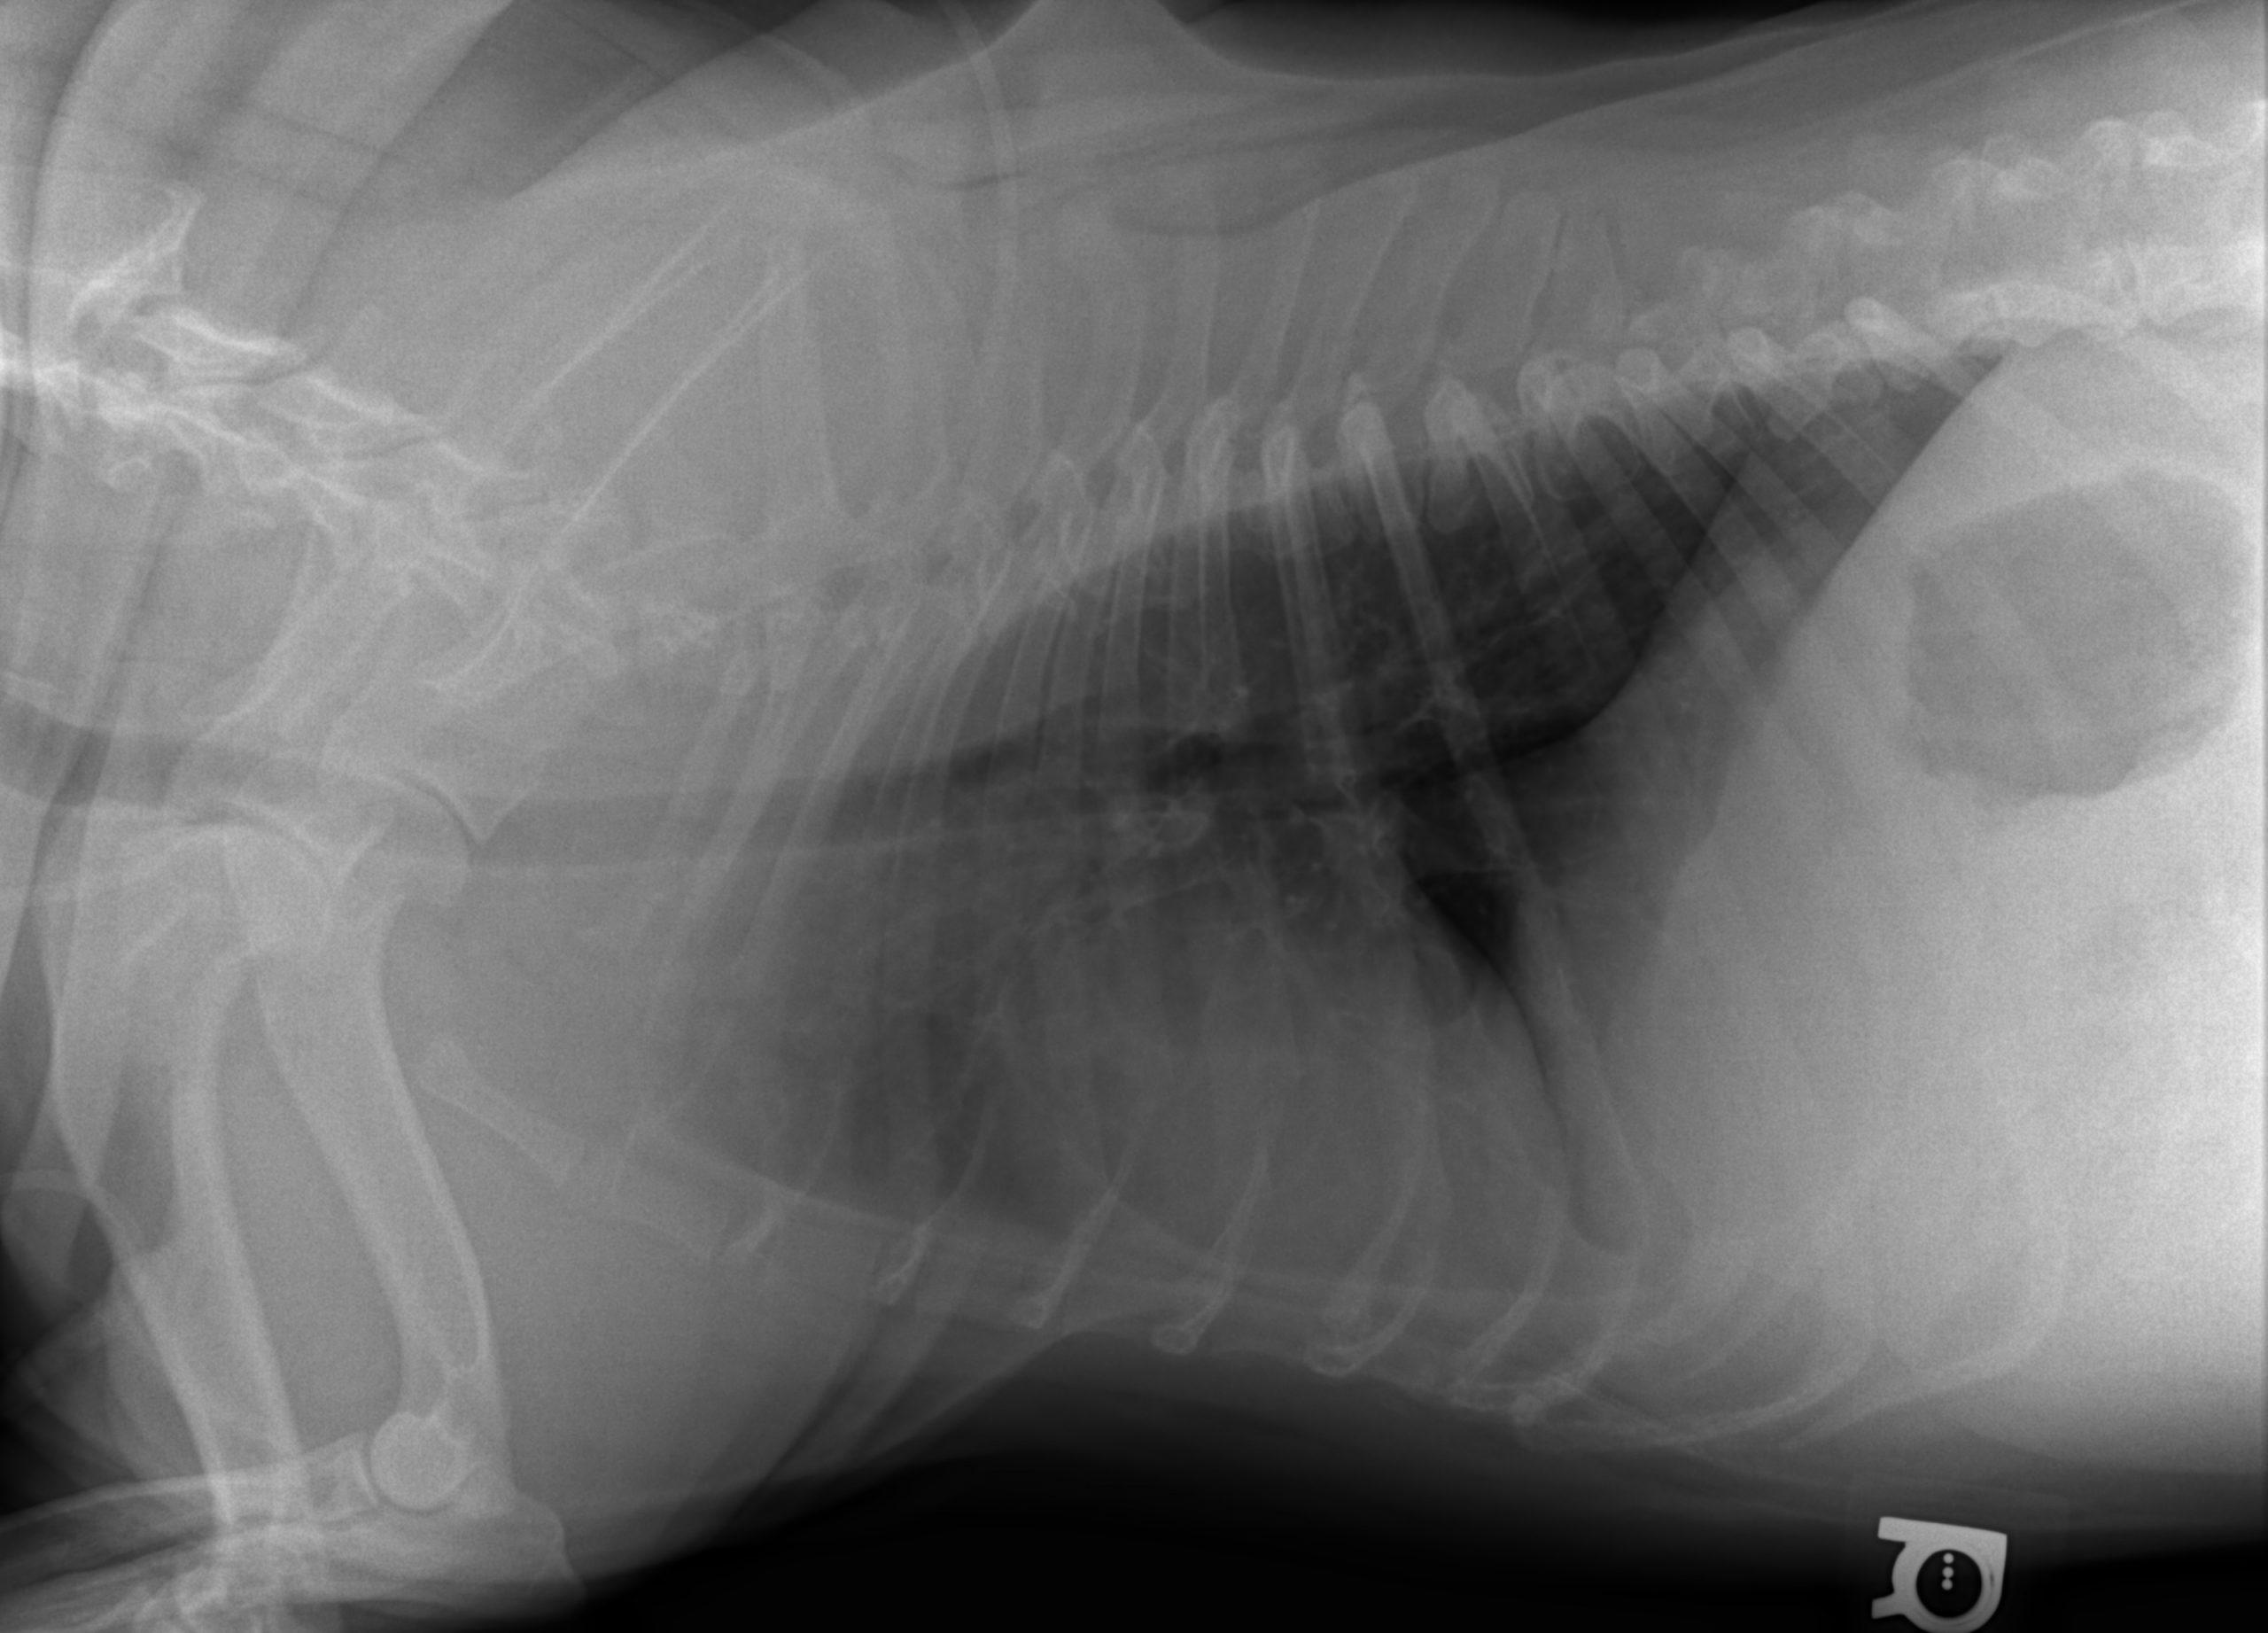

A 6-year-old intact male English Bulldog was presented for 2-3 days of intermittent vomiting and lethargy. Physical exam found the patient to be tachycardic with pale mucous membranes and a palpable mass in the abdomen. Serum biochemistry revealed elevated alkaline phosphatase, hypernatremia, and mild hypochloremia. On CBC, a decreased HCT in conjunction with a high MCV was noted, in addition to a neutrophilia, monocytosis and thrombocytopenia. No abnormalities were noted on thoracic radiographs. Abdominal radiographic findings revealed a loss of contrast in the cranial abdomen, with the possibility of a splenic mass. Radiographic Interpretation showed marked splenomegaly strongly suspected to be secondary to torsion, although accompanying infiltrative or neoplastic pathology could not be ruled out. The small volume of peritoneal effusion and inflammation was likely secondary to the splenic pathology. Thoracic radiographs showed mild microcardia and under perfused pulmonary vasculature in support of hypovolemia. Atypical intrathoracic fat distribution was considered to be incidental in this dog. This dog had multiple hemivertebrae.